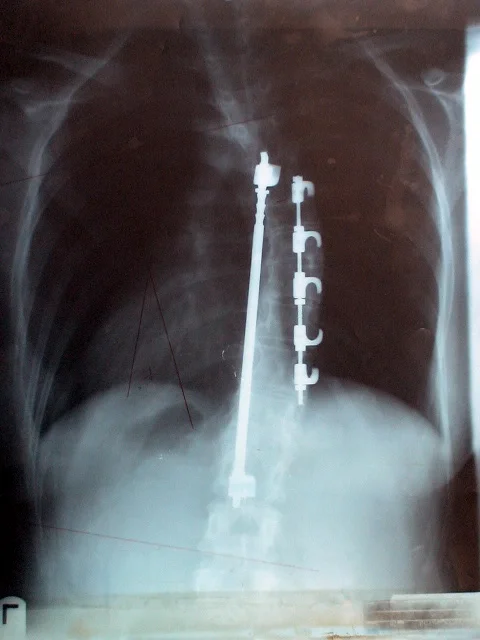

1. Harrington Rod

Paul Randall Harrington (1911–1980) was an American orthopaedic surgeon best known as the designer of the Harrington Rod, the first device for the straightening and immobilization of the spine inside the body. Using metal rods and hook instrumentation, this surgery was used regularly in the 1960s and remained the gold standard for scoliosis surgery until the late 1990s. During this period, over one million people benefited from Harrington's procedure.

It is interesting to note that in 1963, Harrington stated, "Metal does not cure the disease of scoliosis, which is a condition involving much more than the spinal column”.

Harrington Rod, Martha Carter